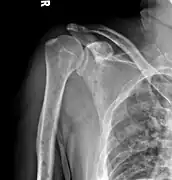

Multiple myeloma in the upper arm

Humerus with multiple myeloma lesions

Same humerus before, with just subtle lesions